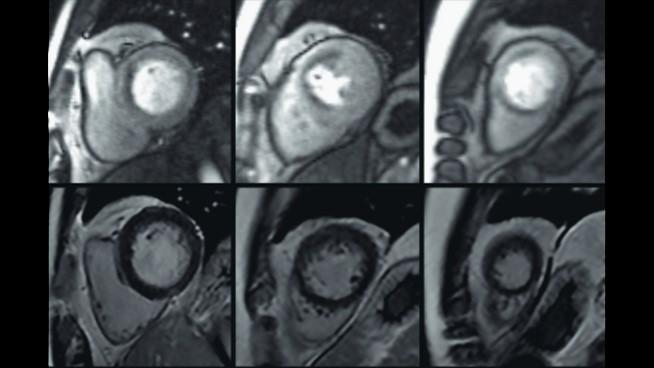

Compressed Sensing & PSIR HeartFreeze

Compressed Sensing Cardiac Cine and PSIR HeartFreeze for functional and LGE imaging in free breathing.

Image acquired with MAGNETOM Sola (1.5T)

Courtesy: St. Georg Hospital, Leipzig, Germany. Study-ID: 1aaaa2598